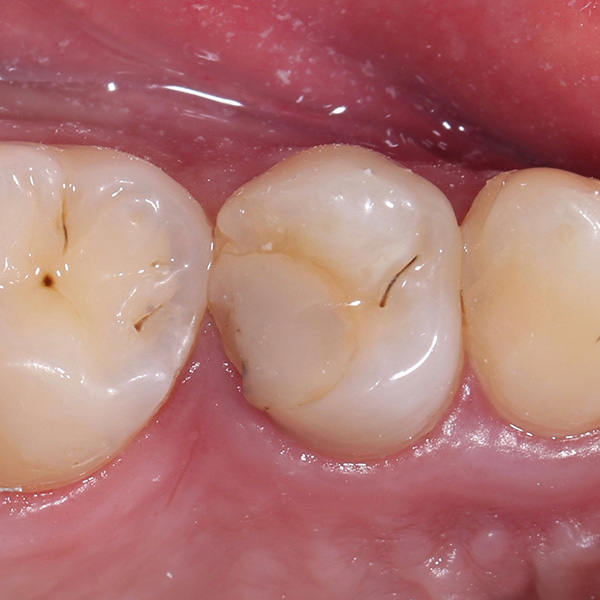

Bei der Versorgung von tief zerstörten, wurzelkanalbehandelten Zähnen mit Endokronen wird defektorientiert und minimalinvasiv vorgegangen. Im Gegensatz zu Präparationen für Vollkronen hat bei Endokronen der Substanzerhalt höchste Priorität. Dafür braucht es jedoch CAD/CAM-Werkstoffe wie das Hybridkeramikmaterial VITA ENAMIC, das in solchen Fällen sehr grazile Rekonstruktionen mit geringen Wandstärken ermöglicht und dessen Werkstoffeigenschaften ein zahnähnliches Verhalten aufweisen. Im vorliegenden Fall wurde die Hybridkeramik auch deshalb ausgewählt, weil sie sich aufgrund hoher Kantenstabilität präzise CAM-technisch verarbeiten lässt und eine sichere adhäsive Befestigung nach bewährtem vollkeramischem Protokoll ermöglicht.

Zahnärztin Dr. Oxana Naidyonova zeigt anhand des folgenden Fallbeispiels Schritt für Schritt ihre Vorgehensweise bei einer VITA ENAMIC multiColor Versorgung.